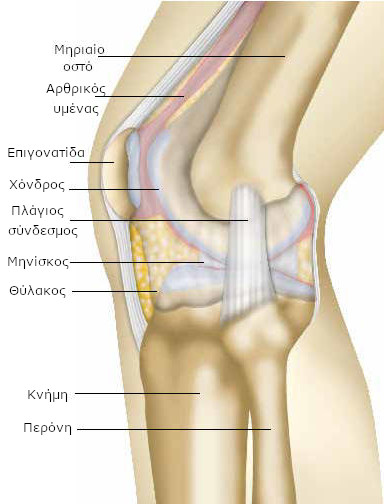

Το γόνατο ενώνει το μηρό με την κνήμη. Το μηριαίο είναι το οστό του μηρού. Η κνήμη είναι το οστό που βρίσκεται κάτω από το γόνατο, στο μπροστινό μέρος του σκέλους, ενώ η περόνη βρίσκεται προς τα έξω και πίσω. Η άρθρωση του γόνατος αποτελείται από το κατώτερο τμήμα του μηριαίου οστού (μηριαίος κόνδυλος) και το ανώτερο τμήμα της κνήμης (κνημιαία γλήνη).

Η επιγονατίδα αποτελεί το τρίτο οστό της άρθρωσης του γόνατος. Συγκρατείται από το μυ του μηρού (τετρακέφαλο μυ) και βρίσκεται στο πρόσθιο τμήμα του γόνατος.

Τα οστά καλύπτει μια μαλακή επιφάνεια (ο χόνδρος) και τους επιτρέπει να γλιστρούν μεταξύ τους.

Οι πιέσεις που ασκούνται στο χόνδρο της επιγονατίδας είναι σημαντικές, κυρίως όταν καθόμαστε στις πτέρνες, ανεβαίνουμε ή κατεβαίνουμε σκάλες, σε ορισμένα αθλήματα κτλ. Οι μηνίσκοι είναι μικρά μαξιλαράκια με ημισεληνοειδές σχήμα που βελτιώνουν την επαφή του χόνδρου του μηριαίου οστού με την κνήμη και συμβάλλουν στην απορρόφηση των κραδασμών.

Βρίσκονται στην εσωτερική και εξωτερική πλευρά του γόνατος (έσω και έξω μηνίσκος αντίστοιχα). Μια μεμβράνη καλύπτει το εσωτερικό της άρθρωσης (αρθρικός υμένας). Αυτή η μεμβράνη εκκρίνει ένα υγρό (το αρθρικό υγρό) που διευκολύνει την κίνηση (λιπαντικό), όπως το λάδι τα γρανάζια μιας μηχανής. Ένας σάκος (αρθρικός θύλακος) περιβάλλει τις περιοχές ολίσθησης και συγκρατεί το αρθρικό υγρό. Γύρω από το σάκο βρίσκονται οι σύνδεσμοι, ένα είδος ανελαστικής κορδέλας, των οποίων ο ρόλος είναι να συγκρατούν στη θέση τους τα δύο μέρη της άρθρωσης